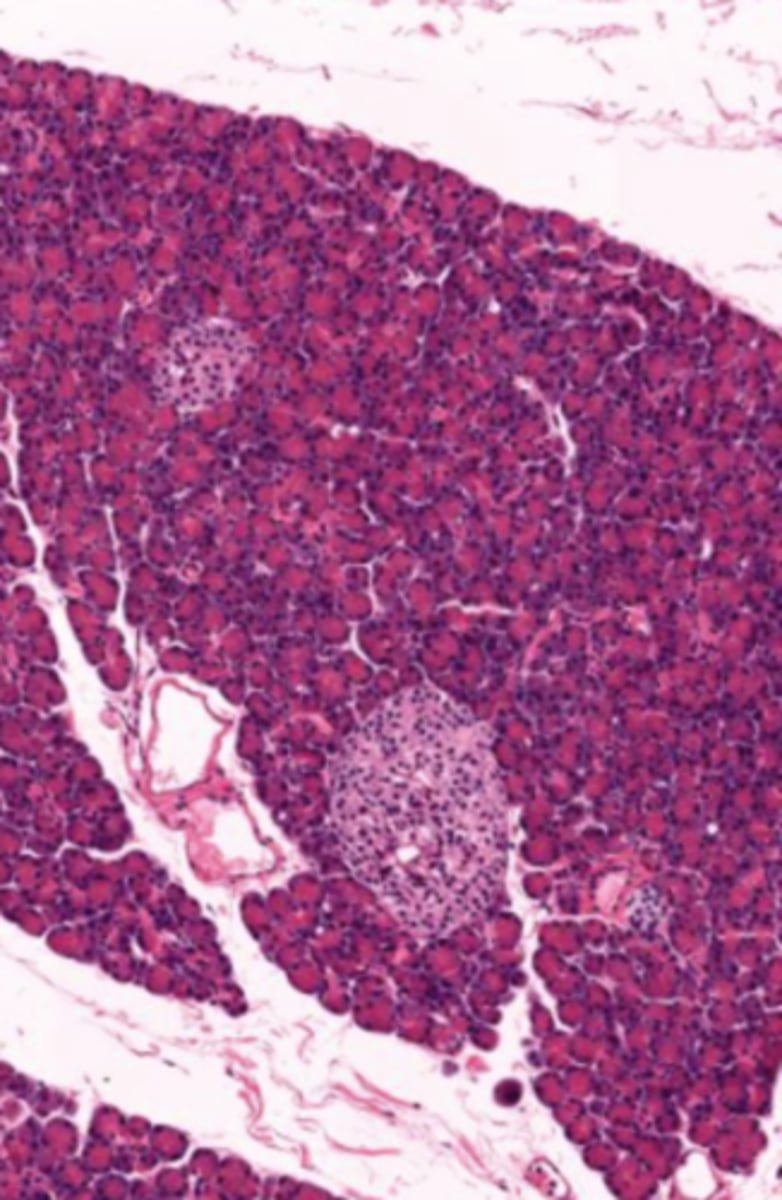

pancreas (histology)

islet of Langerhans (pancreas)

Acinar cells (pancreas)